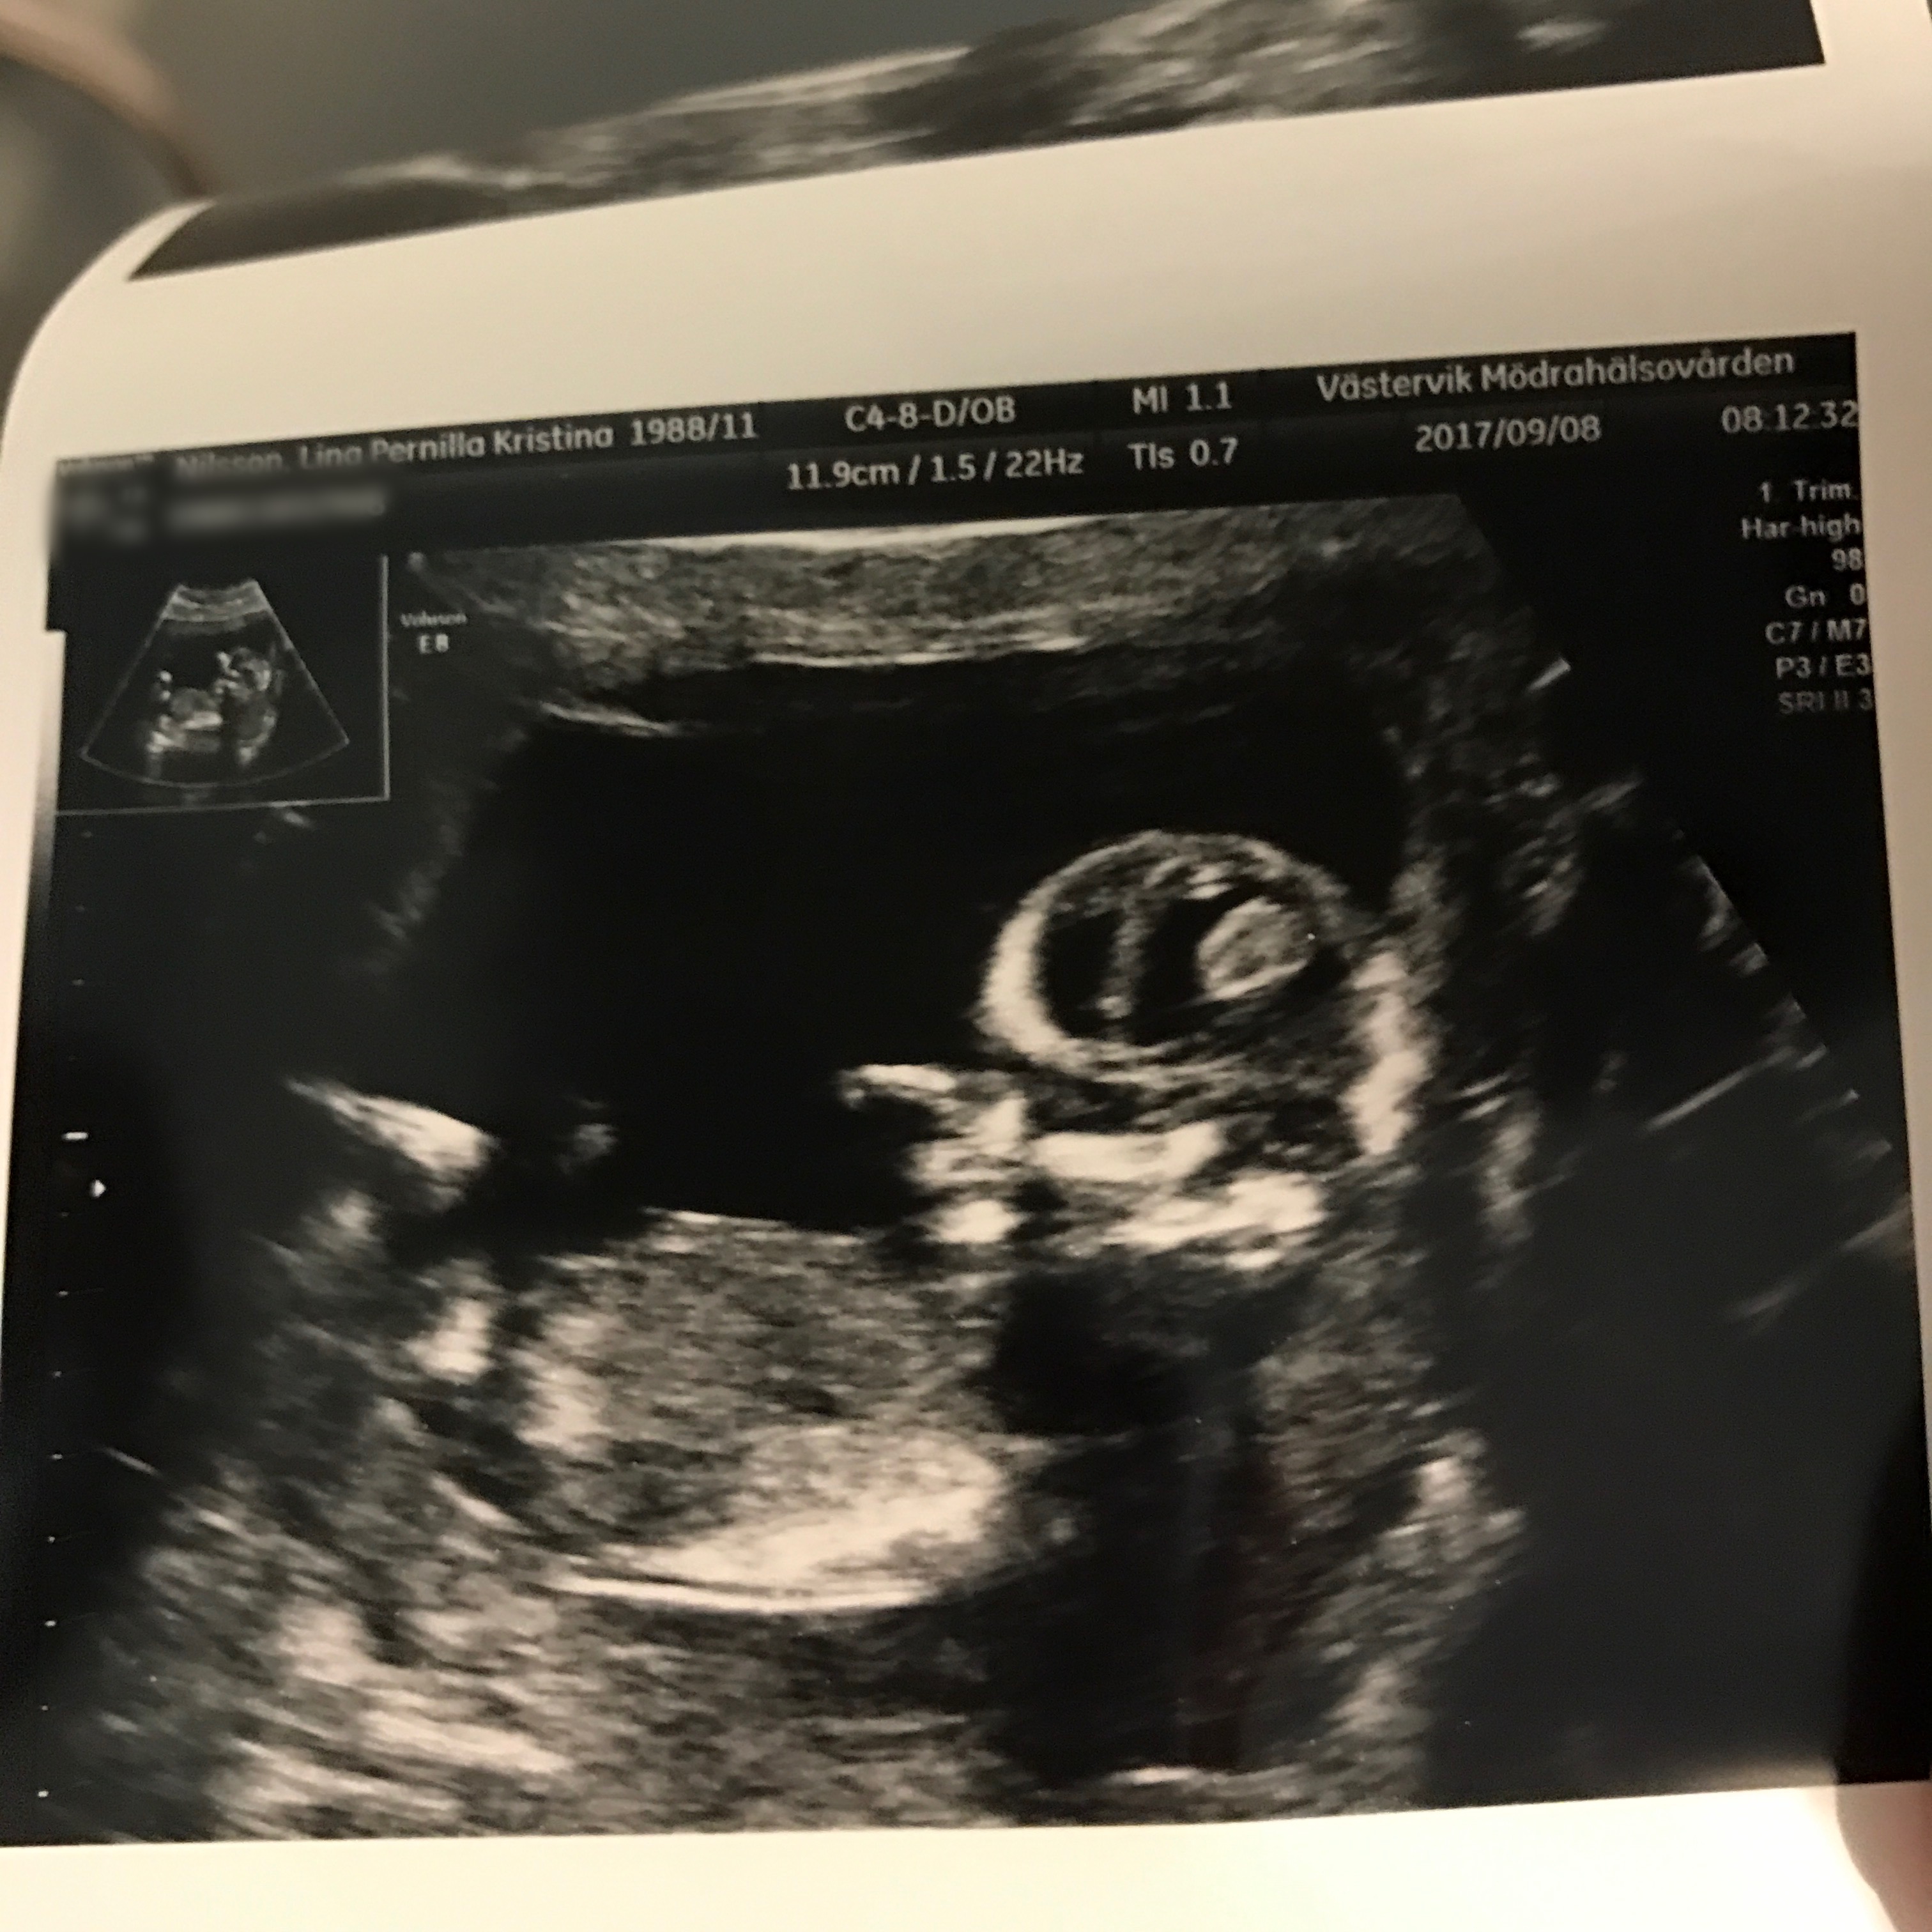

Det jag ser fram emot mest är att fixa i larvens rum. Som tur är får vi (förhoppningsvis) veta i slutet på oktober om det är en liten kille eller tjej som gömmer sig där inne (i min mage alltså, i rummet hoppas jag att det inte är någon som gömmer sig).